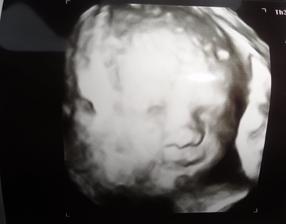

O anjelikovi a srdiečku

Mojko drzte sa z babuskom v brusku..uz to mate za par .. o chvilu budete spolu..album je nadherny.krasna spomienka na anjelika.neviem sa dockat ked sa drobec narodi...ako vznikne pre Tvoju rodinku novy obrazok.

Ked vidim fotky v tvojom albume mam slzy v ociach, krasny obcas smutny ale tak plny lasky!!! moc moc vam drzim prsty nech si donesiete domov ten najkrajsi darcek . Pri tvojom albume si uvedomujem strasne vela veci aj ked som z krpcov niekedy na nervy dakujem bohu,ze su tu s nami a zdravi. Uz le chvilku a drobcek nude s vami a moj tip je ze to bude dievcatko 😊.